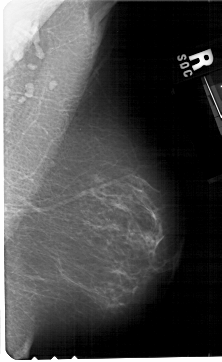

A_1479_1.LEFT_MLO

LEFT_MLO LINES 5491 PIXELS_PER_LINE 3466 BITS_PER_PIXEL 12 RESOLUTION 43.5 OVERLAY